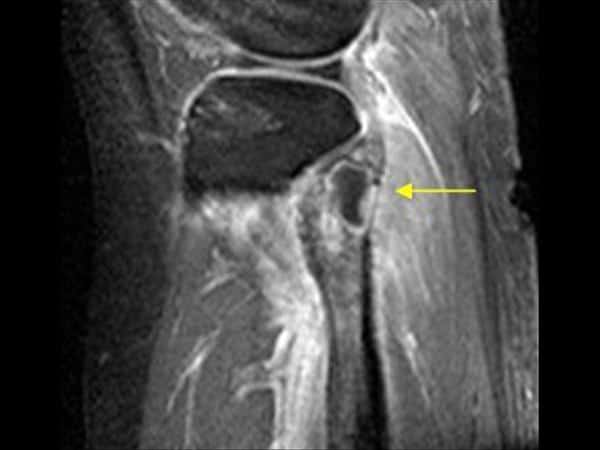

Apxe Brodie

Apxe Brodie + Mất liên tục màng xương

Apxe Brodie + Mất liên tục màng xương - Phù nề mô mềm

Viêm xương tủy

» Thông tin: Nam giới – 34 tuổi.

» Lâm sàng: Sưng đau khớp gối.

# Apxe Brodie / Mất liên tục màng xương – Phù nề mô mềm.